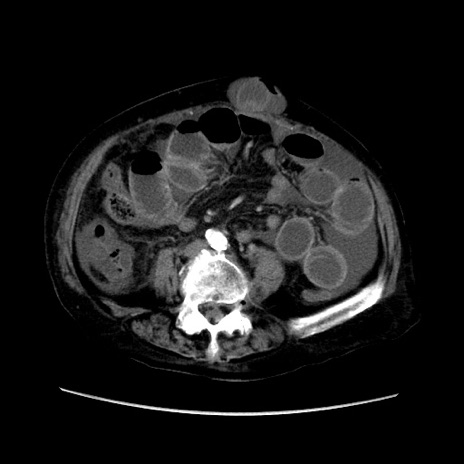

症例31(横断像)

【症例】80歳代 女性

【主訴】腹部膨満感

【現病歴】他院にて肝硬変にてフォロー中。1週間前から便秘、腹部膨満感、臍部腫瘤あり受診となる。

【既往歴】肝硬変

【身体所見】腹部膨隆あり、皮膚変化なし、疼痛なし。

【データ】WBC 4600、CRP 0.25